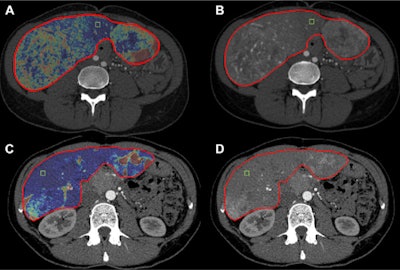

CECT does this by allowing clinicians to track patients' liver-enhancing tumor burden (LETB), wrote a team led by Dr. Jessica Assouline of the University of Paris in France.

"Volumetric tumor enhancement assessment has been shown to help predict survival in patients with cancer," the group noted. "[But] rather than a lesion-by-lesion volumetric analysis, volumetric assessment of metastatic disease in the entire liver, also known as the liver enhancing tumor burden, is a more comprehensive marker of tumor response in neuroendocrine liver metastases after intra-arterial treatments."

The team sought to evaluate CT's efficacy for this indication, conducting a study that included 119 patients with neuroendocrine liver metastases who underwent 161 intra-arterial procedures between April 2006 and December 2018. The group evaluated treatment response using the Response Evaluation Criteria in Solid Tumors (RECIST) and modified RECIST (mRECIST) tools, as well as the level of LETB on contrast-enhanced CT imaging, tracking patients' overall survival, recording the time from initial treatment until the time when intra-arterial treatments were considered untenable, and calculating hepatic and whole-body progression-free survival.